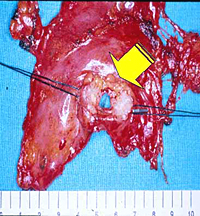

The lower half of the gland is then retracted upward and the thymic veins, usually two or three, are identified clipped and divided (Figure 5). Subsequently, the dissection proceeds cephalad, superior to the innominate vein, into the lower cervical region. The superior horns are progressively dissected free by blunt maneuvers with the aid of gentle traction applied downward on the thymus. In this way, even long and thin upper horns can be dissected en bloc with the rest of the gland. The intact thymus is extracted in a retrieval bag through the most anterior port and is examined to ensure that the whole gland has been removed (Figure 6).

Patients with thymomatous MG are usually operated on through the transsternal approach; however, small (< 3cm in size) encapsulated thymomas incidentally discovered during VATS thymectomy can be safely excised en bloc with the thymic gland through this approach (Figure 11).